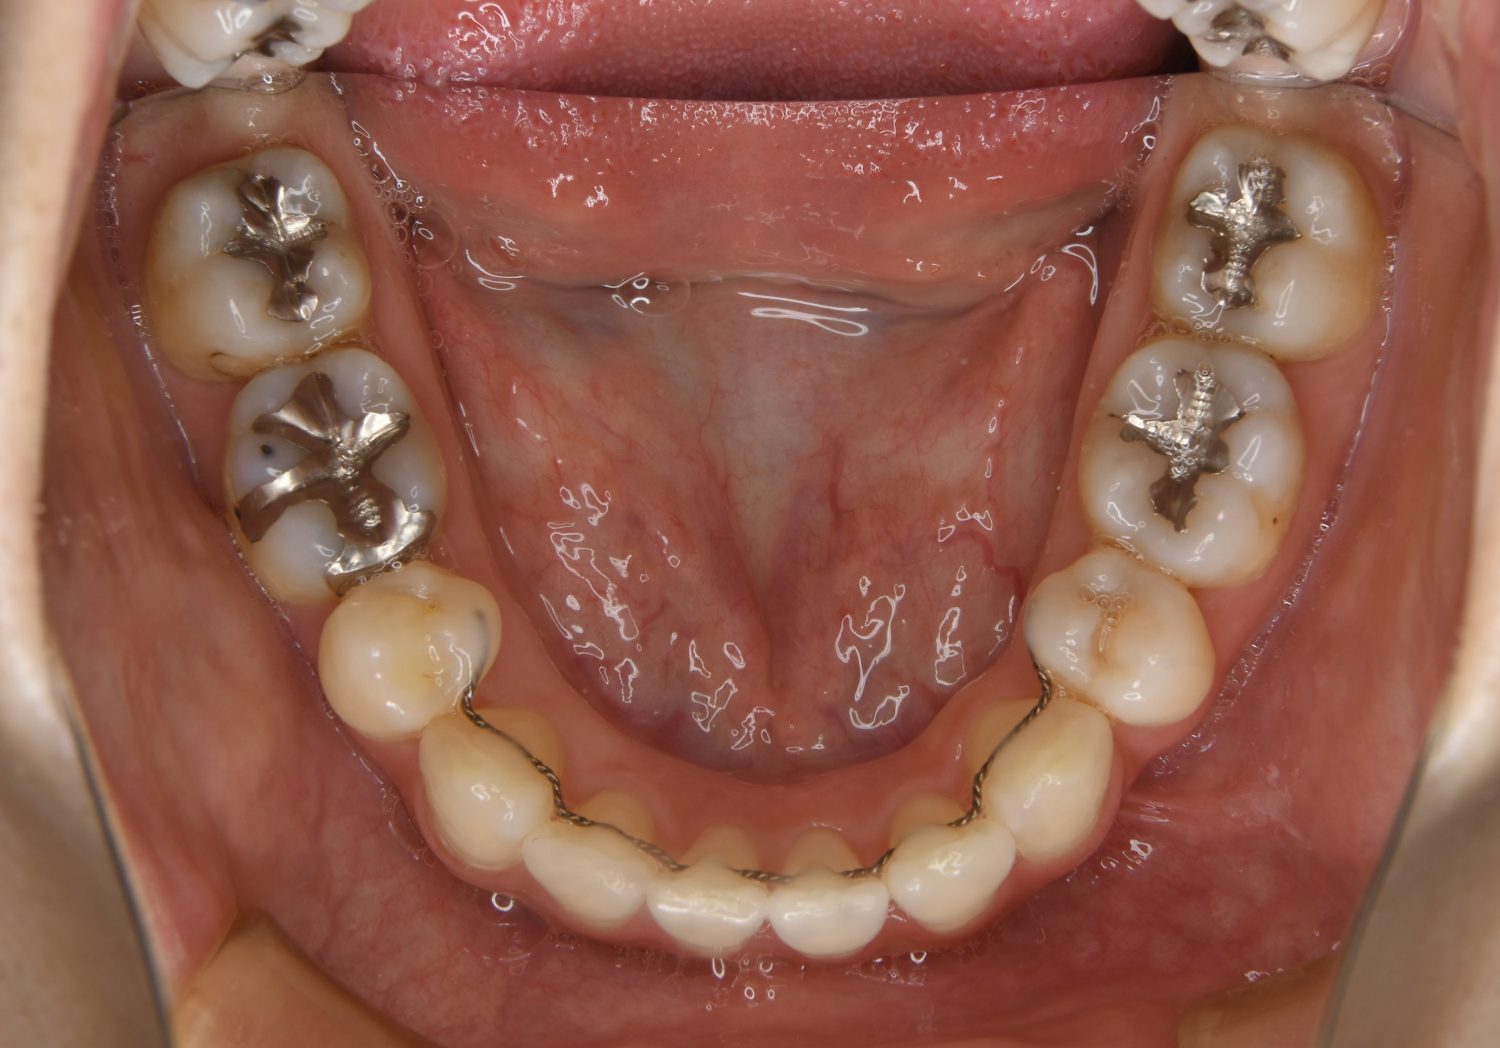

前歯部開咬の症例紹介②

Before

主訴

前歯で物が噛めない

治療内容

上下ラビアルブラケット(唇側装置)に矯正用アンカースクリューを併用し非抜歯で治療を行いました。

治療費

1,000,000 円(税込)

治療期間

26ヶ月

通院回数

27回

想定されたリスク

※歯根吸収、歯肉退縮、歯髄壊死、顎関節症状

上下の前歯が開いており前歯では全く噛めていない状態でした。臼歯の圧下を行うことで機能面のみでなく審美面も改善しました。